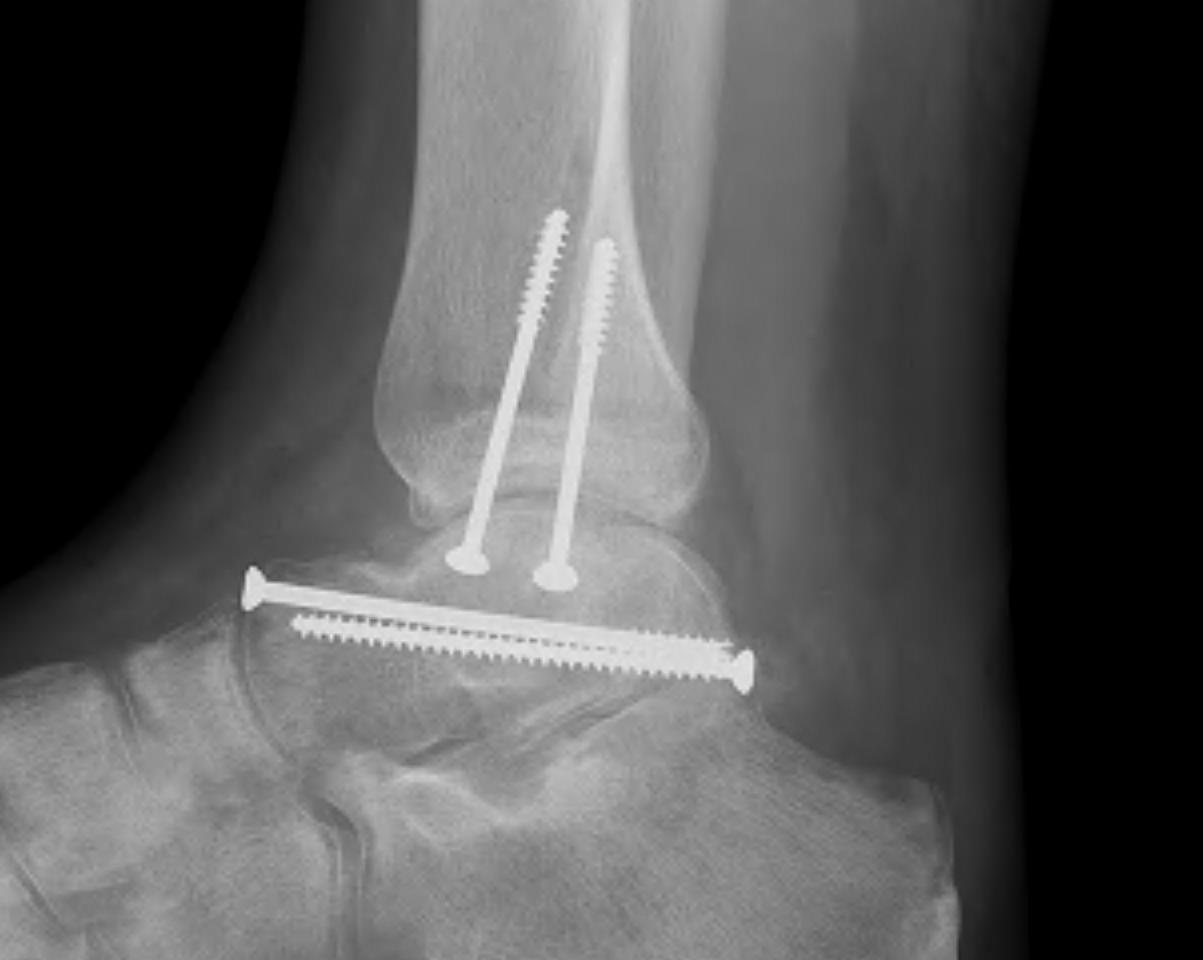

talus fracture

Talus fracture (95) 사진